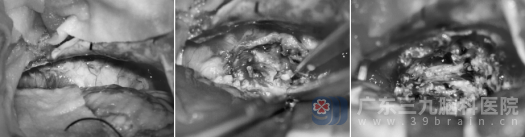

面对这一病例,神经外十科迅速组织多学科会诊。考虑到肿瘤较大,已压迫周围神经结构,手术治疗是最佳选择。在完善术前准备后,由欧阳辉教授及樊雁峰主任领衔的团队为王某实施了左侧桥小脑角区肿瘤显微切除术。

手术在高清显微镜及神经电生理监测下进行,以最大限度地保护面神经和听神经功能。经过数小时的精细操作,肿瘤被完全切除。术后复查MR提示:肿瘤无残留,已完全切除。术后病理结果也证实了术前判断:(桥小脑角区肿瘤)神经鞘瘤, CNS WHO 1级,属于良性肿瘤。